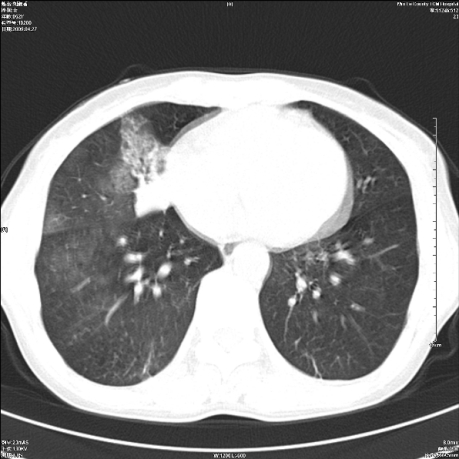

标题: CT19625:女52间断性喀血 [打印本页]

标题: CT19625:女52间断性喀血

考虑右肺中叶感染性病变并右肺中、下叶肺泡积血;建议抗炎、止血治疗后复查。

右肺中叶炎症;右肺中、下叶肺泡积血

右肺中叶支气管扩张并感染或咳血沉积,块右肺中下叶肺泡积血。

右肺中叶慢性炎症伴局部支扩并中下叶肺泡积血。

考虑右肺中叶感染性病变并右肺中、下叶肺泡积血。建议治疗后复查。